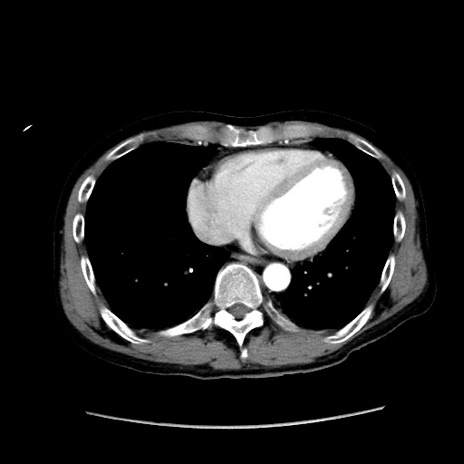

症例37(横断像)

【症例】40歳代 男性

【主訴】腹痛

【現病歴】4時間ほど前に電車に乗車中に臍部上より腹痛出現。徐々に増悪し起立困難となり、救急外来受診。生ものは数日食べていない。今朝お雑煮を食べた。

【身体所見】BT 36.8℃、BP 117/84mmHg、HR 91/min、SpO2 97%、苦悶様、腹部:臍上部広範囲圧痛あり、反跳痛±

【データ】WBC 8100、CRP 0.03